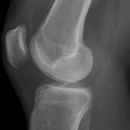

Kniegelenk seitlich

Beurteilungskriterien

• Blumensaatlinie: ( = entspricht dem Dach der Fossa intercondylaris) Patella alta: unterer Pol >3cm über Blumensaat Linie

• Insall-Salvati-Index: Die Relation zwischen Patellahöhe (Vertikaldurchmesser) und Länge des Lig. patellae liegt zwischen 0,8 - 1,2.

• Patellasehnenruptur => Patella alta => Insall-Salvati-Index < 0,8, Quadrizepssehnenruptur => Patella bacha => Insall-Salvati-Index >1,2, häufig jedoch keine signifikante Patellaverschiebung

• Femoropatellares Gleitlager: Gelenksspaltweite <5mm, Cave: medialer Femurkondylus größer als Lateraler, zudem ist der Laterale flacher als der Mediale, kommen nicht zur Deckung.

• Ergusszeichen: Erguß kann einziger Röntgenbefund bei osteochondralen Frakturen, Kollateralbandrissen, Kreuzbandverletzungen, Meniskusverletzungen sein -> MRT

• Flüssigkeit-Fett-Spiegel in der Bursa suprapatellaris -> intraartikuläre Fraktur

• Flüssigkeit-Luft-Spiegel -> offene Verletzung

• Muskelfettlagen -> Fettkörper darf nicht abgehoben sein: M.rectus femoris, M.vastus intermedius, ventrales Femurmetaphysenfettpolster, suprapatellares Fettpolster, Fettlage dorsal des Gelenkspaltes